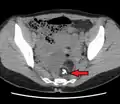

A small (4 cm) dermoid cyst of an ovary, discovered during a C-section